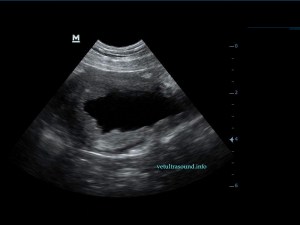

Η πάχυνση του τοιχώματος και η δοκίδωση του βλεννογόνου είναι εμφανής σε όλες τις εικόνες. Πολλές φορές οι λαγόνιοι λεμφαδένες μπορεί να είναι ήπια διογκωμένοι και να έχουν αντιδραστική ηχομορφολογία. Ο έλεγχος με έγχρωμο Doppler του τοιχώματος της άδειας κύστης μπορεί να μας δείξει ροή αίματος στα αγγεία της κύστης. Αντίθετα, είναι πιθανό, όσο η κύστη γεμίζει με ούρο η ροή αίματος να μην είναι ορατή με το Doppler. Αυτό συμβαίνει συχνά στη χρόνια βακτηριακή κυστίτιδα λόγω της ίνωσης του τοιχώματος της ουροδόχου και αυτή είναι μία από τις αιτίες της μη ανταπόκρισης στη θεραπεία. Η συγκεκριμένη παθοφυσιολογία έχει μελετηθεί στον άνθρωπο με την βοήθεια ενδοσκοπικού υπερήχου.

The increase of thickness of the urinary bladder wall and the striation of the mucosa is evident. Inguinal lymphnodes are usually prominent and mildly enlarged. Colour Doppler may reveal the blood flow of the mucosa of the empty urinary bladder, whereas the blood flow in a full bladder appears decreased. This could be because of the fibrosis of the urinary bladder wall and could explain why sometimes chronic conditions like these do not respond well to antibiotics. This pathophysiology has been studied in humans with the use of endoscopic ultrasound.